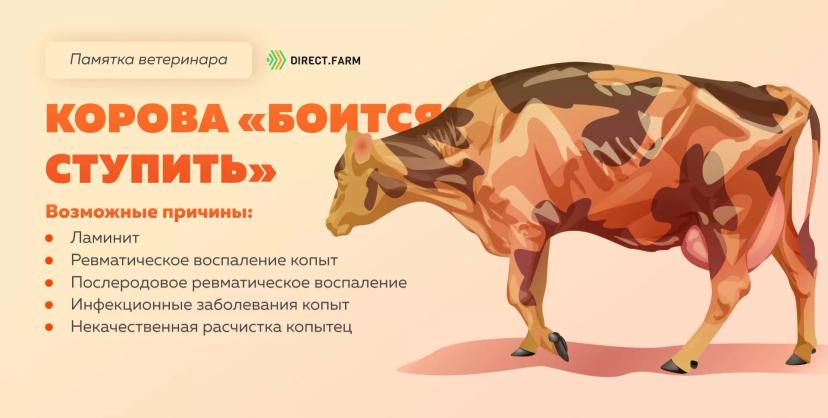

Памятка ветеринара: коровы идут как будто «боятся ступить»